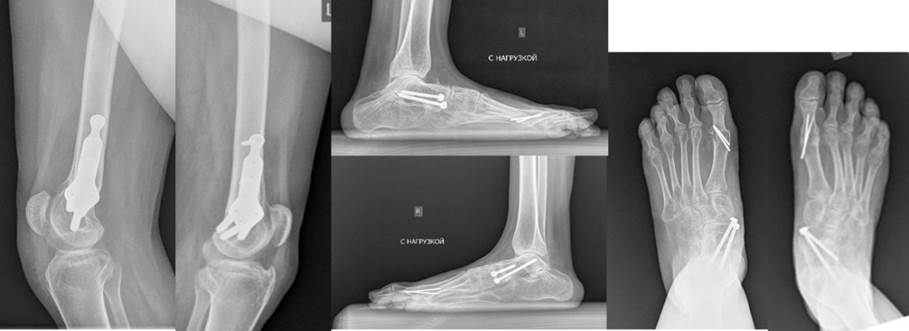

CROUCH GAIT („hodanje na polusavijenim kolenima“)

Karakteriše fleksija kolena veća od 15° u vreme inicijalnog kontakt faze oslonca ciklusa koraka, kao i trajni položaj stopala u položaju dorsifleksije, fleksija kuka, koja se često kombinuje sa intratorzionim deformitetom butne kosti, spoljašnja rotacija stopala u odnosu na vektor kretanja pacijenta zbog teškog plano-valgusa deformiteta stopala sa izuzetno izraženom abdukcijom prednjeg dela i/ili spoljnog torzionog deformiteta kostiju potkolenice, karlica može biti u normalnom položaju ili nagnuta unazad

Ekstenzija nogu postignuta

Spuštanje patele

Produženje mišića odgovornih za kontrakture

Otklanjanje deformiteta stopala

Brzo samostalno hodanje

Nema potrebe za šetačima

Dobri uslovi za dalju rehabilitaciju